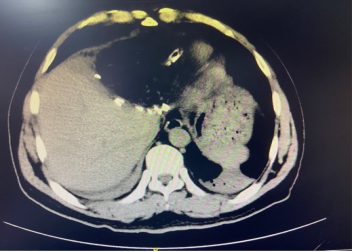

陆朝阳告知患者,肝脏肿瘤巨大,CT显示约25cm,诊断为巨大肝癌,经过门诊初步评估,存在手术切除甚至微创切除的可能。患者和家属终于见到了一丝希望。

上图左为肝脏增强CT所示肝肿瘤,上图右为肝脏CT三维成像技术

术后复查CT,显示肿瘤完整切除